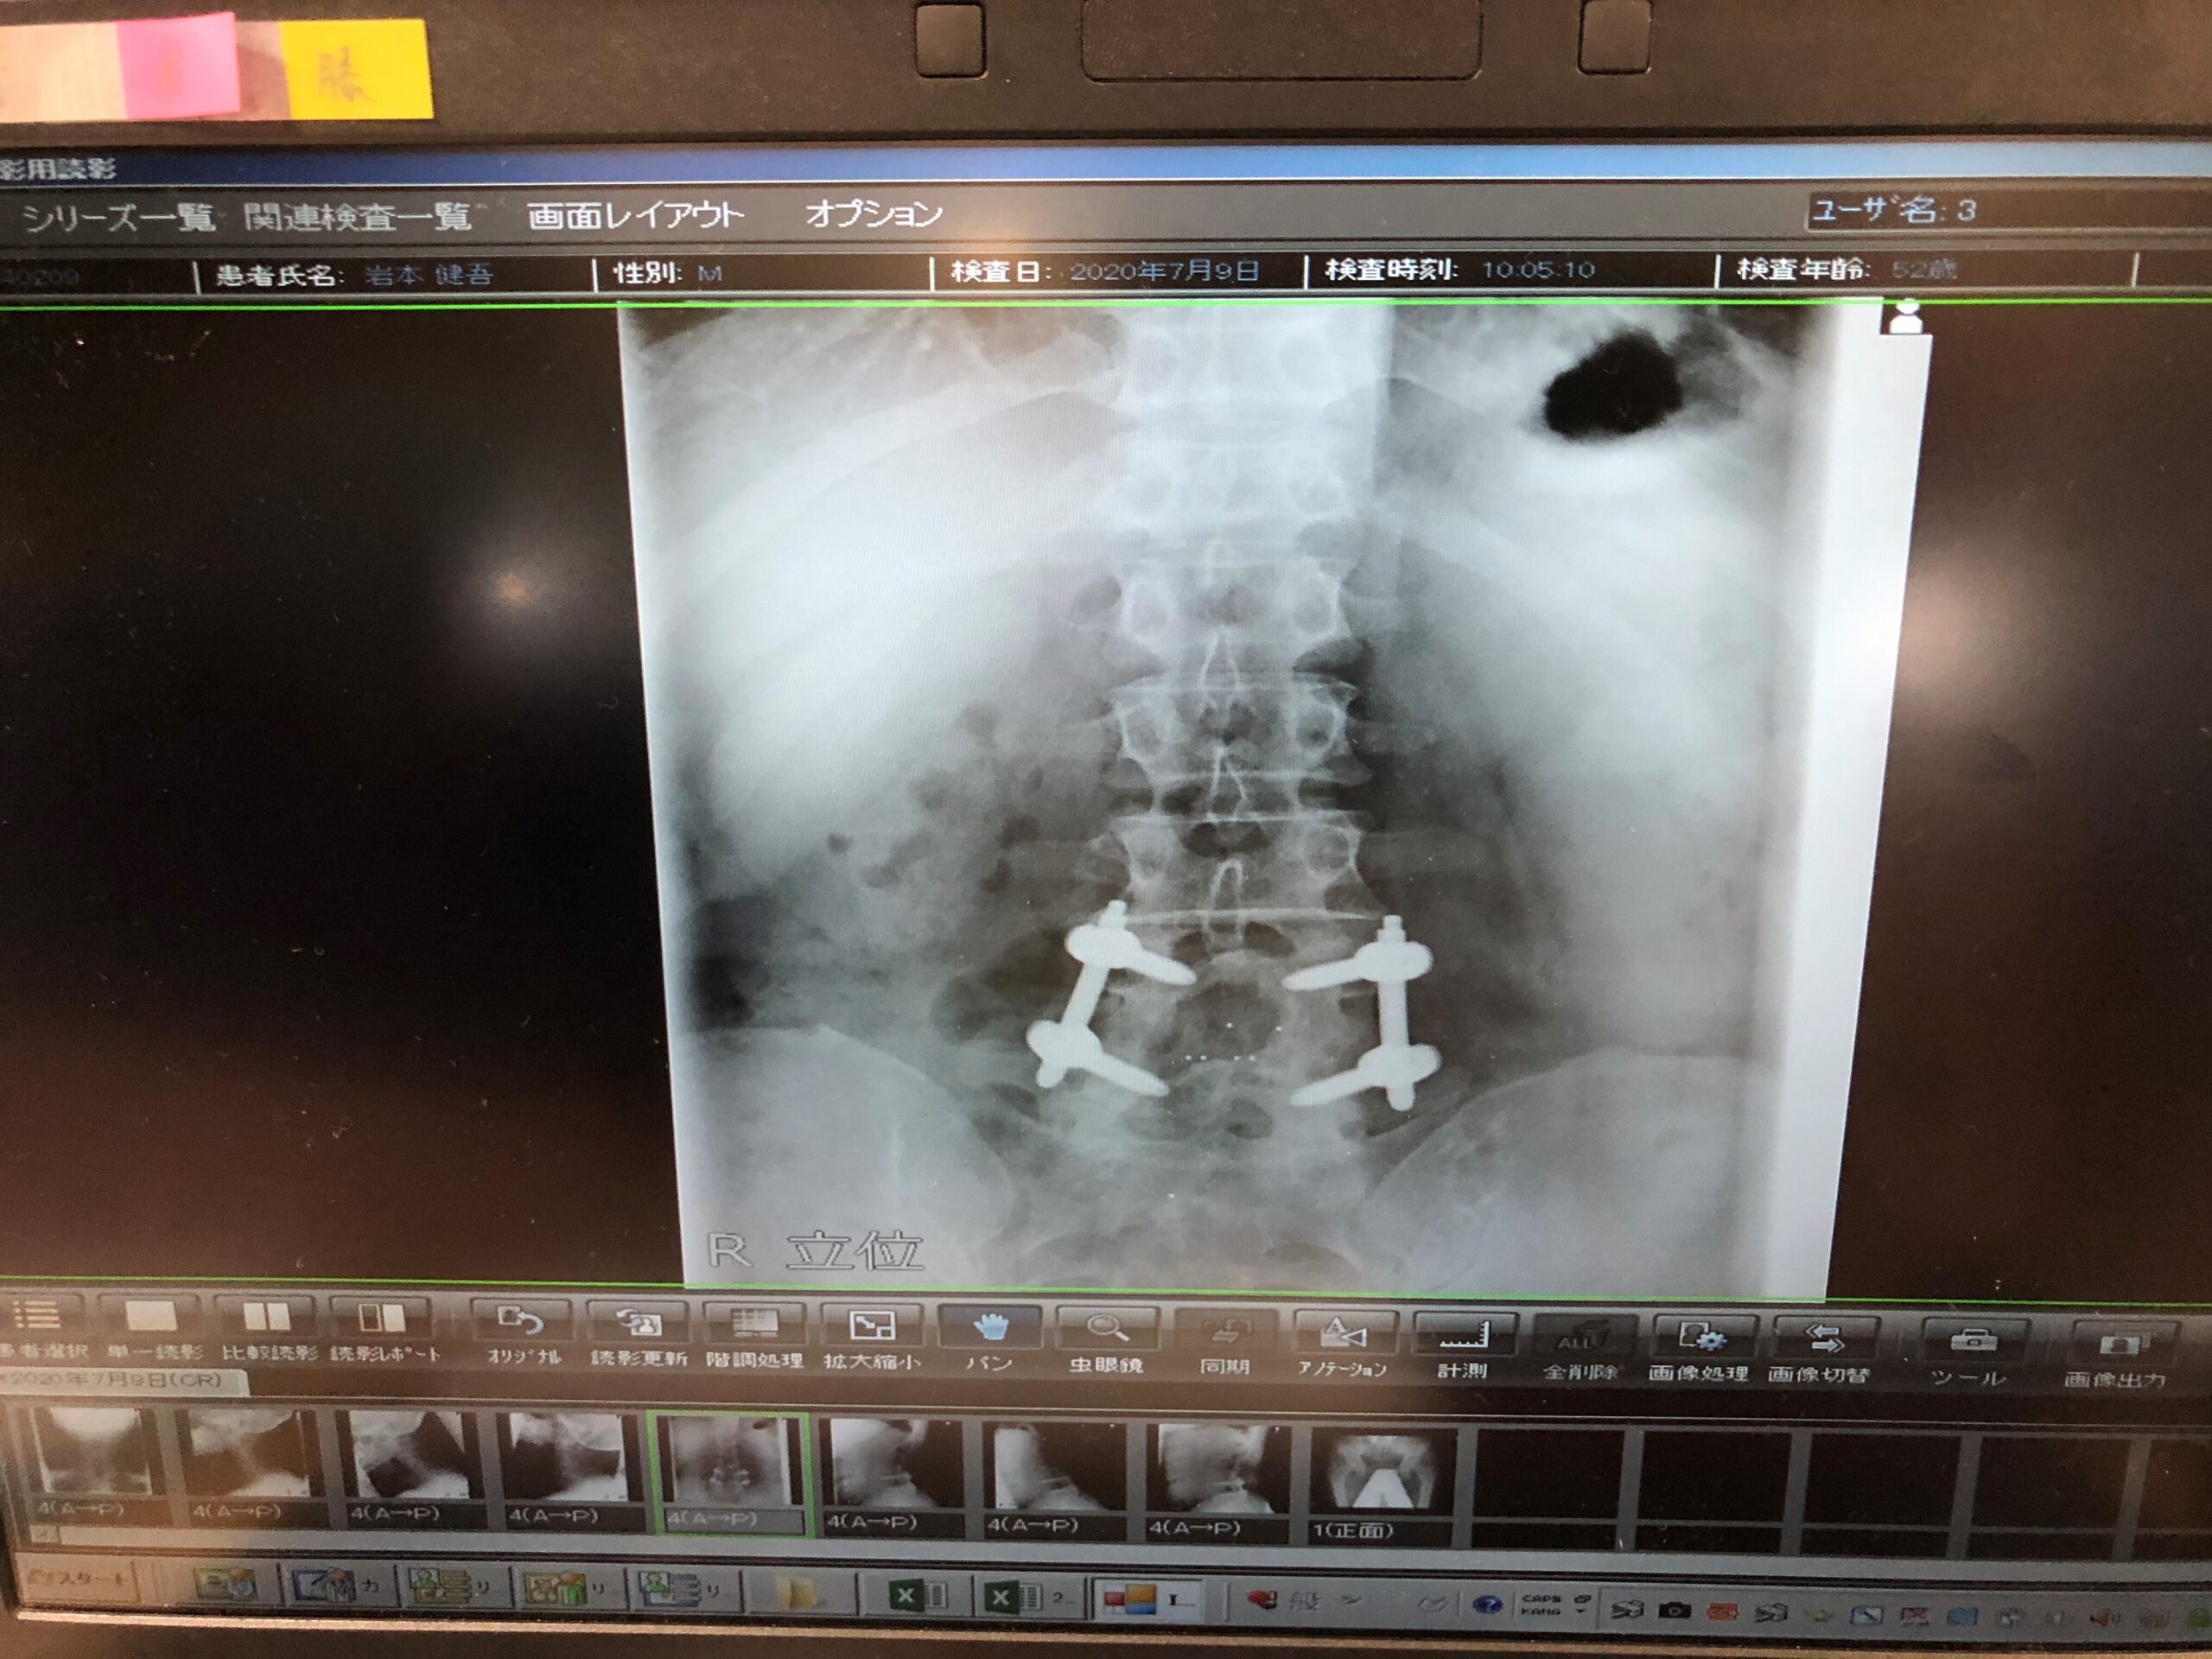

一気に自分が大きな手術した時に戻った💦

しかも35針縫うて

ボルトも埋まったまま

背骨は固定されてうまく体を動かせない